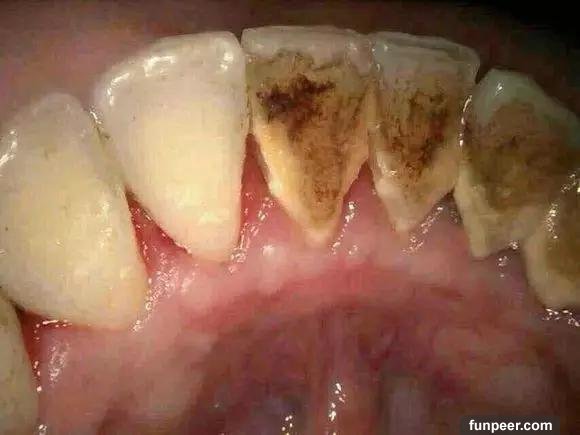

什麼是牙結石牙結石又稱牙石,通常存在於唾液腺開口處的牙齒表面。如下顎前牙的舌側表面,上顎後牙的頰側表面和牙齒的頸部,以及口腔黏膜運動不到的牙齒表面等處。牙結石最開始是乳白色的軟垢,通過逐漸鈣化變硬。它是由75%的磷酸鈣,15%~25%的水、有機物、磷酸錳、礦酸鈣及微量的鉀、鈉、鐵所構成。牙結石通常呈現出黃色、棕色、或黑色等,有的與自然牙顏色相近,有的則明顯可見差異。

與口水濃度有關,濃度愈大,愈易沉澱。另外,牙結石形成的速度、形態和硬度因人而異,一般來說新生牙結石只需12-15小時。快速形成的牙結石要比慢慢形成的牙結石要軟且碎。牙結石的危害牙結石一旦鈣化,就等同於在口腔中落地生根,建立了生存的基地。但這位大惡魔並不會就此止步,而是繼續開枝散葉、呼朋引伴,隨著時間的推移越積越多、越級越厚,並逐漸向牙頸部位發展,形成更為隱形也更為可怕的“齦下結石”。

牙結石從牙冠逐漸向下蔓延,牙結石每進步一些,牙槽骨就萎縮一些,久而久之,牙齒就逐漸松動,牙結石便見縫插針,逐漸蔓延到牙根部位。對口腔而言,結石是一種異物,它的存在本身就會不斷刺激牙周組織並壓迫牙齦,影響口腔局部血液循環,造成牙周組織病菌感染,引起牙齦發炎萎縮,形成牙周袋。當牙周袋形成後,食物殘渣、牙菌斑和結石等更易堆積,進一步的破壞更深的牙周膜,如此不斷的惡性循環的結果,終至牙周支持組織全部破壞殆盡,牙齦出血、牙周疾病等隨之而來。總而言之,如不能及時清除,被牙結石纏上的牙齒最終逃脫不了潰爛脫落的命運。作為口腔健康的一級殺手,牙結石的存在不容忽視。值得注意的是,在牙結石形成之初由於硬度較小,使用口腔清潔或刷牙等方法往往較容易清除,而隨著日積月累的鈣化、牙結石在口腔中緊密附著,普通的刷牙或口腔清潔方法便難以將其去除了。相信有的朋友在閱讀文章的時候就已經按耐不住“攬鏡自照”來確認自己口中有沒有被牙結石入侵了吧?不用過分擔心,接下來將傳授給大家對抗之法,幫助大家戰勝這位牙周疾病的罪魁禍首、口腔中的大惡魔。牙結石的清除方法經過鈣化的牙結石難以通過刷牙等傳統方式清潔,但口腔潔治可以做到,也就是通常說的洗牙。洗牙有手工掛治和超聲潔治兩種,目前大部分醫院和診所采用的是超聲潔牙。手工刮治通過比較精細的齦下刮治器刮除牙齒附著的牙石和菌斑。而超聲潔牙機則通過高頻率震蕩傳導至特制工作尖,將能量集中在工作尖並釋放,對頑固堅硬的牙結石產生較大的衝擊力,並將其震碎,使其從附著的牙面脫落。同時,超聲震蕩產生的水霧將環繞在工作尖的周圍,將牙結石的碎屑衝洗殆盡。